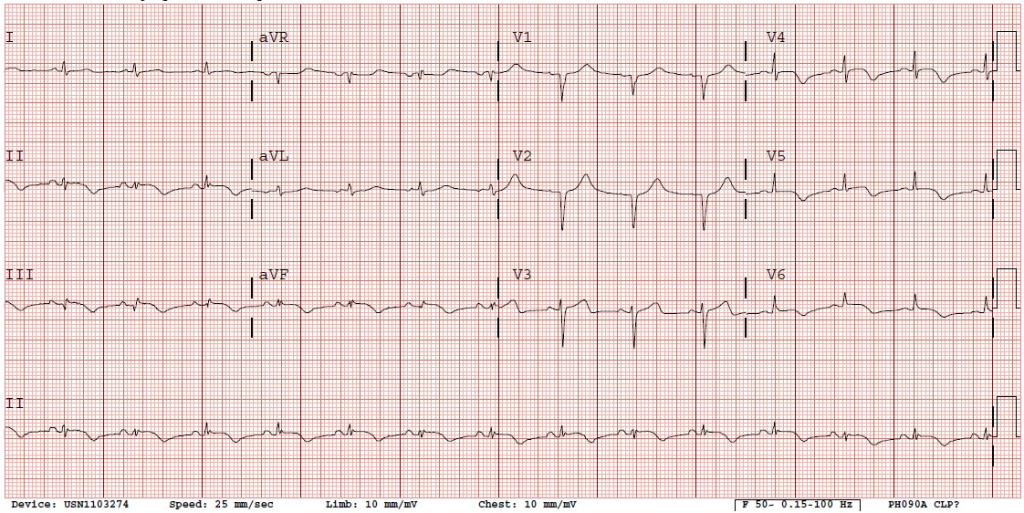

Een 68-jarige patiënte met acuut pijn op de borst. Wat ziet u op het elektrocardiogram?

Op het elektrocardiogram ziet u een sinusritme 80/min.

De hartas is niet duidelijk te bepalen.

De PQ-tijd meet 160msec, QRS-duur 90 msec en QT-tijd 400 msec.

Er zijn opgetrokken ST-segmenten in de onderwandsafleidingen II, III en aVF met negatieve T-toppen.

Er is afwezigheid van R-progressie in V2-V3 en de T-toppen zijn eveneens negatief in V4-V6.

Opmerkelijk is dat zowel de inferior als de anterior leads “ischemische” afwijkingen vertonen.